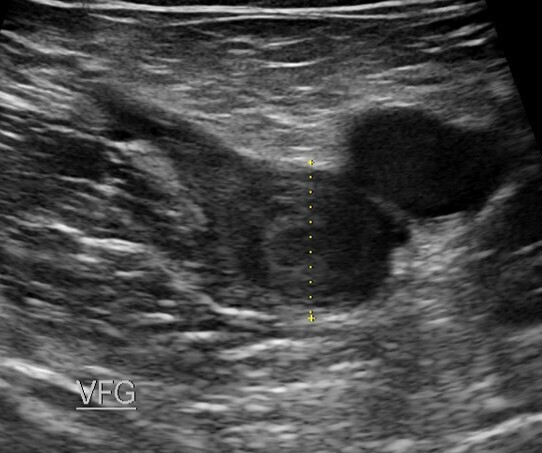

Dès lors que le patient est anticoagulé efficacement et porte sa compression médicale de classe 2 (classe 3 peu utilisable et en plus non portée), les patients doivent marcher. Il s'agit d'une marche chaque jour de 4000 à 6000 pas. Cependant il faut expliquer aux patients les bienfaits de la marche.

La localisation sus-inguinale, thrombose iliaque, voire ilio-fémorale est à l'origine d'une gêne à la marche avec un retentissement sur la qualité de vie , c'est attendu.

Les thromboses proximales, notamment iliaques, sont sur le plan de l'hémodynamique veineuse un obstacle majeur, surtout dans les premiers jours, car la circulation collatérale de suppléance (sus-pubienne) met 15 jours pour se développer. Ceci n'est pas le cas des TVP fémoro-poplitées où les réseaux de suppléance saphéniens sont activés immédiatement. De plus cette obstruction iliaque génère une hypertension veineuse ++++

La marche active quotidienne est vivement recommandée (depuis maintenant 20 ans) avec une compression de classe 2 le plus tôt possible, à la "dose" de 45 mn/jour.

La marche stimule la reperméabilisation du thrombus et à un effet antalgique et anti-oedème.